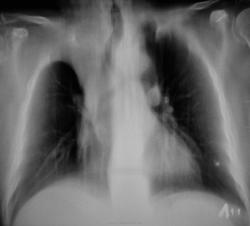

Хотелось бы узнать возраст, клинику, ну и жалобы неплохо было бы. "Попахивает" ателектазом. Мне показалось, что срединная тень сместилась немного вправо, да и контуры затенения уж очень ровные.

Да, тянет на ателектаз, хотя образование может расти и из апикальной плевры, оттесняя легкое. Бронхоскопия.

52 года. Жалоб нет. Сегодня проходила "флюшку", сразу сделали снимки.

Образование, деформирующее нижнюю треть трахеи справа с её оттеснением, вероятно из ВДБ, бисегментарный ателектаз. Прямые томограммы корней, стандартные боковые справа через корень. На томограммах "порезал" бы и задние отрезки рёбер.

Ателектаз верхней доли за счёт образования,которое перекрыло верхнедолевой бронх, смещает главный бронх и трахею.

По данным рентгенологического исследованинаиболее вероятна опухоль правого главного бронха с вовлечением регинальных лимфоузлов.

диагноз будет верифицирован после бронхоскопии. Но, так как у нас идет мозговой штурм по представленным данным классической рентгенографии, выскажу свой генез заболевания у больной. Наличие кальцинатов в легких и во внутригрудных лимфатических узлах с обеих сторон позволяет предположить реактивацию туберкулезной инфекции с развитием туберкулеза внутригрудных лимфатических узлов, активного туберкулеза бронхов со стенозом 3 степени и ателектаза. Такова моя версия. В ПТД сначала, а не к онкологу, чтобы не вызывать стресс у больной.